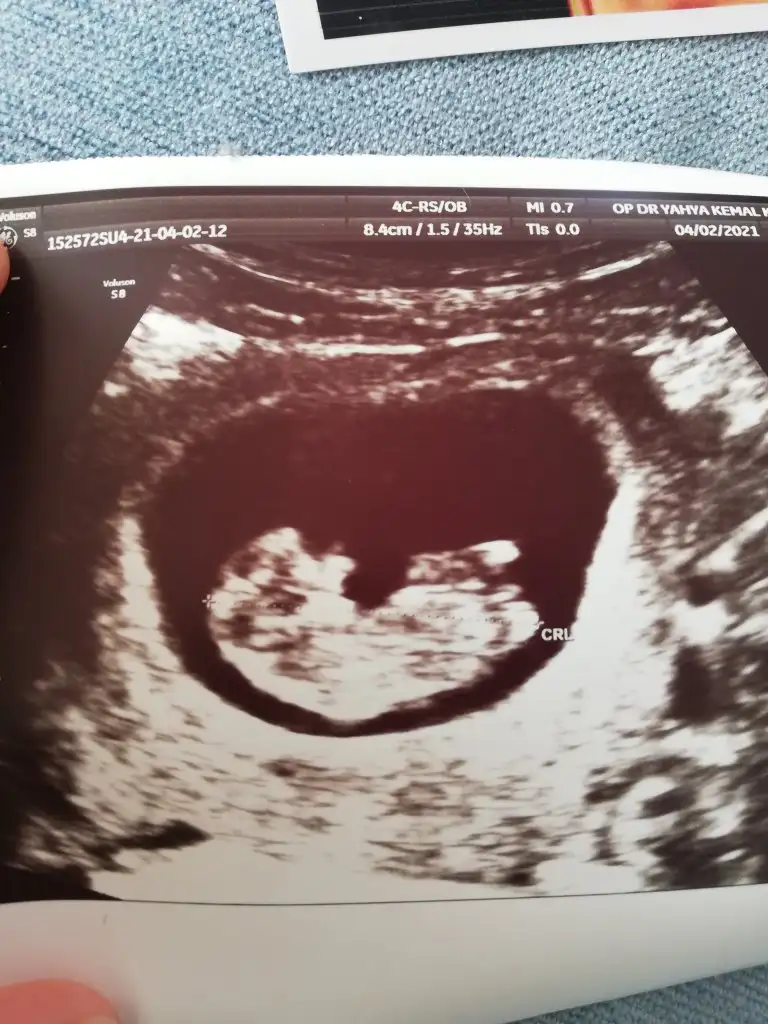

Kız görünüyorIkra meyra 16 haftalık bacak altından sence hangisine yatkın

Kız görünüyor